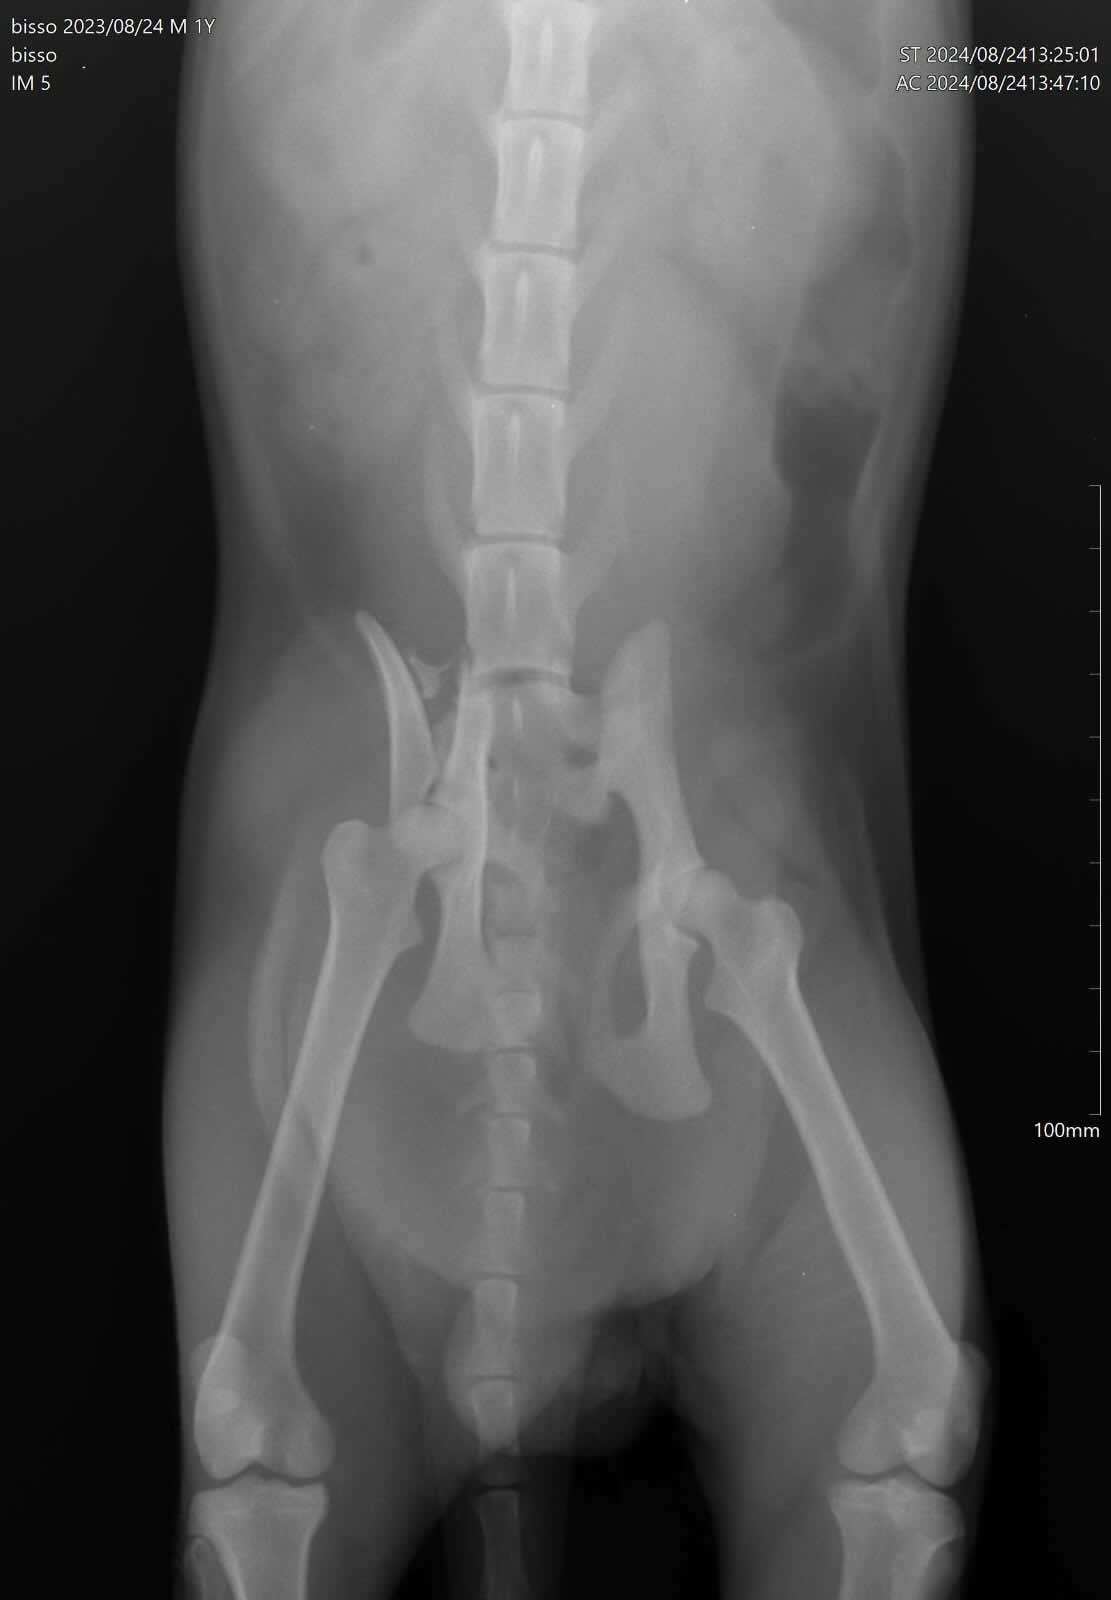

Help Bisso undergo a surgery

Bisso is a stray cat that was hit by a car on the street. The car did not stop to see what happened so I took him and rushed to the vet. The vet said he needs a surgery to his fractured pelvis or he will be paralyzed forever!